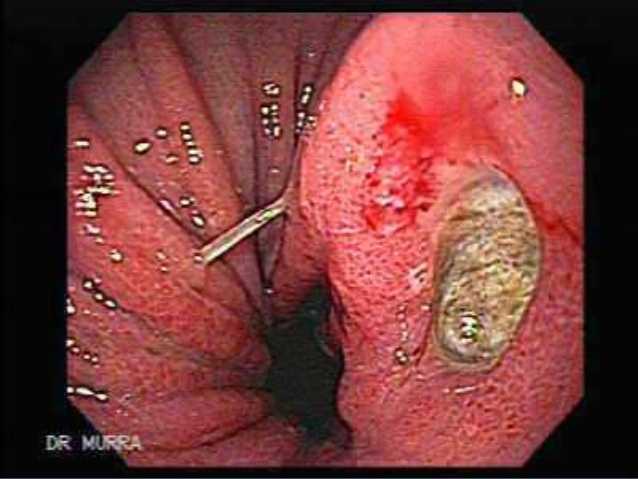

Ülser hastaları ne yemeli ne yememeli, hangi yiyecekler mide ülserine iyi gelir ? Mide ülseri ileri seviyedeki mide hastalıklarında biridir ve mutlaka seçici beslenmeyi gerektirir. Bazı yiyecekler ülser tedavisini destekler, bazıları ise ağrıları artırır. Ülser hastaları ne yemeli Bal Kuranı Kerimde Nahl Suresinde şifalı olduğu bildirilen balın mideye faydalı olduğu bilimsel çalışmalarla da desteklenmiştir. Balın … Devamını oku